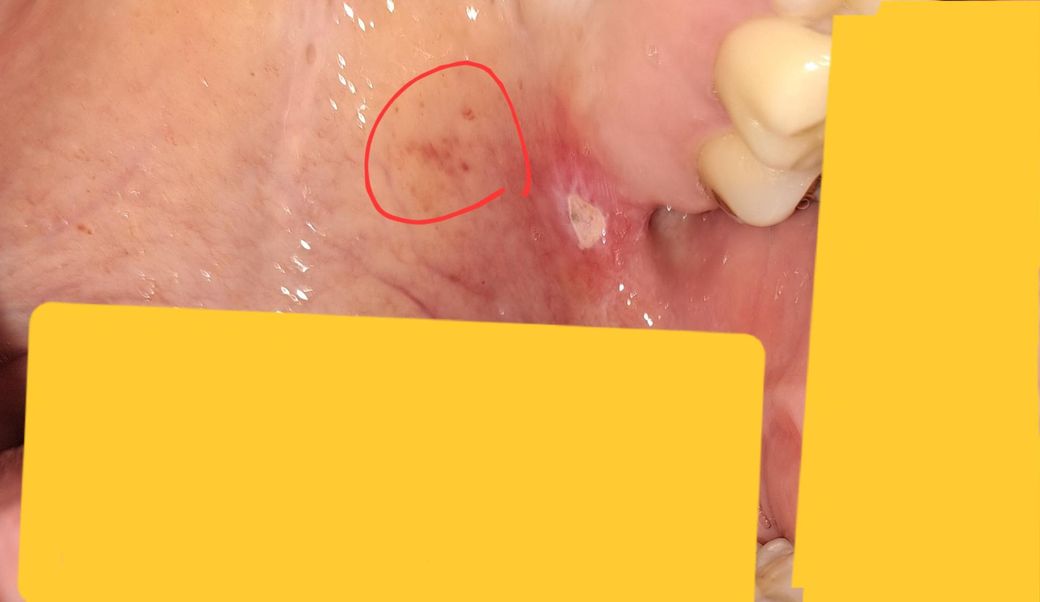

입천장 구내염에 관련된 질문입니다!!

이게 구내염일까요? 저 위치에 나는게 흔한 일인지 모르겠어서요 ㅠㅠ 그리고 보통 구내염은 일주일정도 지나도 낫지가 않으면 병원을 가봐야하는걸까요?

+빨간점들은 면역력이 저하돼서 생긴건지 궁금합니다

• 1번 째 사진

입천장(구개)에도 구내염이 생길 수 있습니다.

혀·입술 안쪽보다는 빈도는 낮지만 스트레스, 면역 저하, 마찰(딱딱한 음식), 상기도 감염 후 등에 의해 그 부위에도 발생합니다.

1) 구내염일 가능성

작은 흰색·노란색 궤양(속이 파인 모양), 주변 붉은 테두리 → 아프다면 구내염 가능성이 높습니다.

입천장은 열감·건조·자극을 많이 받아 낫는 데 다른 부위보다 오래 걸릴 수 있습니다.

3) 주변 빨간 점

국소적인 자극성 점막염

피곤, 스트레스, 수면 부족 등으로 생긴 면역 저하 반응

뜨거운 음식·풍선껌·간식 등으로 생긴 미세 점막 손상

이런 경우가 흔합니다.